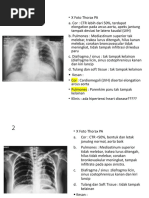

TB PARU AKTIF

Cor tidak membesar.

Sinuses dan diafragma normal.

Pulmo:

- Hili normal.

- Corakan bronkovaskuler normal.

- Tampak bercak lunak di apeks/lapang atas/tengah/bawah kanan/kiri.

KESAN :

- TB paru aktif.

- Tidak tampak kardiomegali.